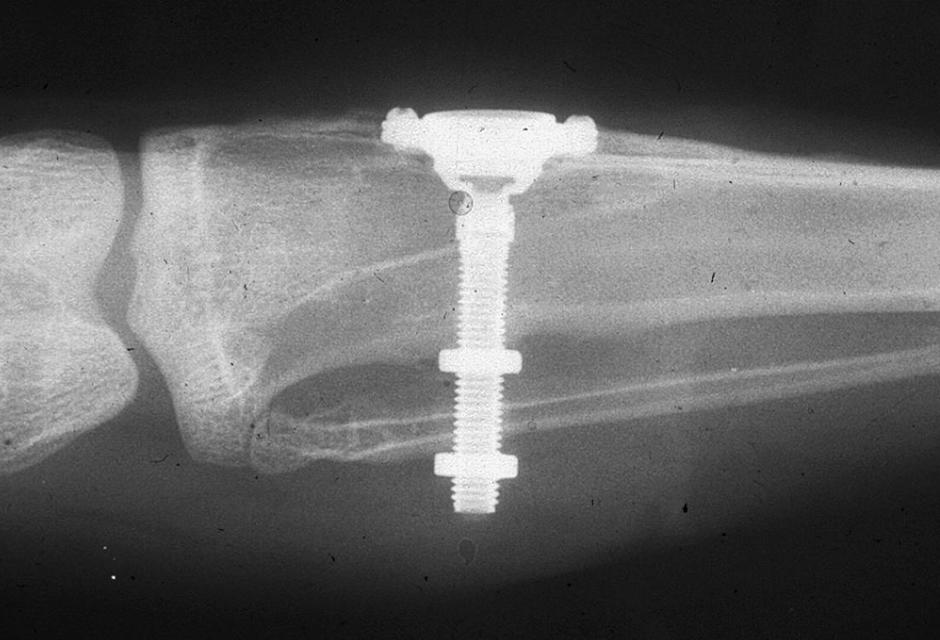

Brånemark's Initial Radiograph